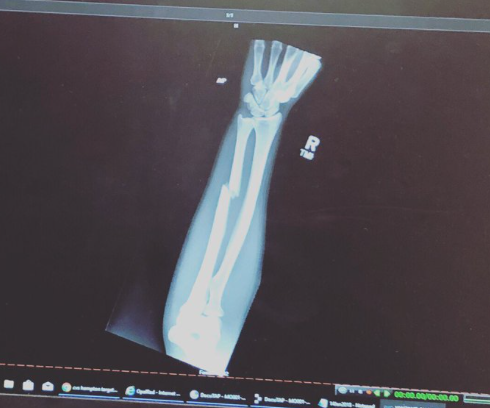

A americana Paige VanZant quebrou o braço direito durante a luta contra australiana Jessica-Rose Clark, nesse domingo (14), no UFC St. Louis.

Apesar da fratura, PVZ mostrou muito coração, continuou no octógono e terminou os três rounds do combate. No fim, foi derrotada por decisão unânime.

Em outra postagem, a peso-mosca (até 57 kg) comentou o vídeo de um trecho da luta no qual aplica um soco giratório em Clark. O golpe, que aconteceu no segundo round — e não no primeiro — foi o responsável pela lesão, segundo a atleta de 23 anos.

No intervalo do segundo para o terceiro assalto, inclusive, a câmera flagrou VanZant citando uma possível fratura no braço para seu córner.